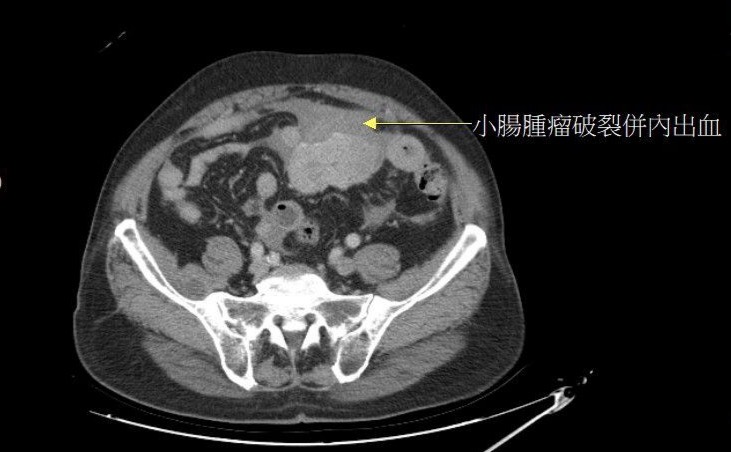

85歲的廖先生因多日不明原因腹痛而到處求診,卻未被診斷出原因,最後因腹痛難耐,無法直立行走,由家人送至大千綜合醫院急診就醫。接受電腦斷層檢查後,赫然發現其小腸處有一個將近10公分的巨大腫瘤,而且已經破裂,造成內出血,經醫師緊急進行開腹手術之後,順利切除小腸腫瘤及部分小腸連接處。病理報告證實為非常罕見的小腸癌,所幸病人術後恢復良好,並持續配合使用口服抗癌藥物。

病人因腹痛就醫,檢查出罕見的小腸癌,且已破裂造成內出血。